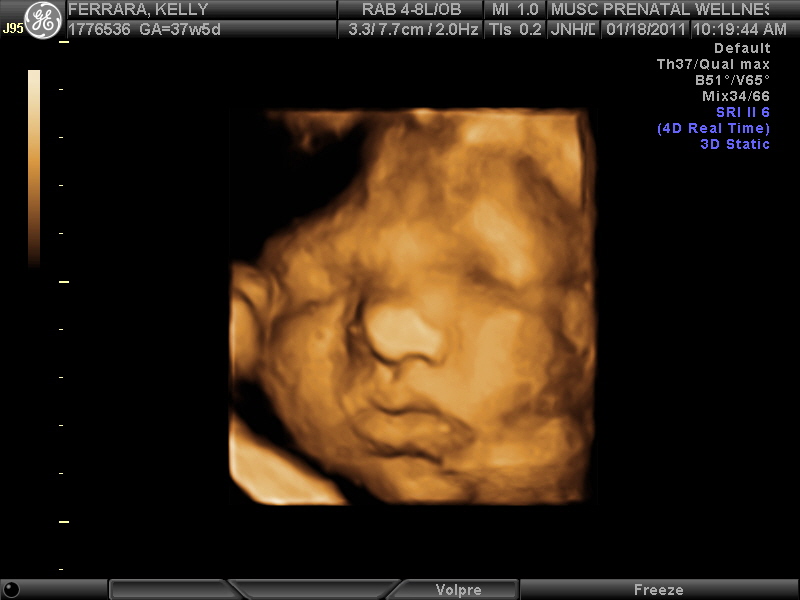

Well I'm not gonna lie... the last couple of days have been awful! I've never been more uncomfortable in my entire life. Back hurts, feet and ankles swollen, can't sit, can't stand, can't walk, can't sleep. The light at the end of the tunnel is getting closer though because I've been scheduled to be induced next Thursday, January 27th! Unless of course the full moon on the 19th brings her early... Oh and of course, at the end of the pregnancy, she finally decided to cooperate during a sonogram so we can finally get a decent picture of her! Here are some of the best ones...